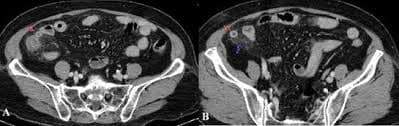

Ca 1: Bệnh nhân 69 tuổi, nữ giới đau hố chậu phải 3 ngày

Ruột thừa viêm hoại tử phần thân và đầu

Hình 1A: A, Hình ảnh ruột thừa to, thâm nhiễm mỡ và tụ dịch xung quanh (mũi tên đỏ). Hồi tràng thành dày viêm phản ứng (mũi tên xanh).

B, Đầu ruột thừa thành không bắt thuốc và mất liên tục, tụ dịch nhiều phần đầu (mũi tên đỏ)

Kết luận: Ruột thừa viêm hoại tử phần thân và đầu